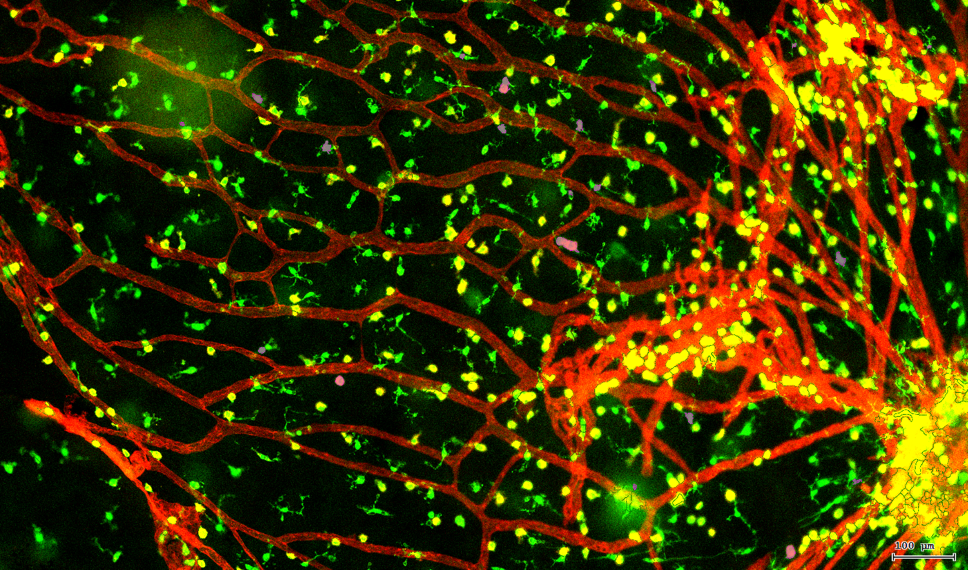

视网膜荧光样本中小胶质细胞胞体、神经纤维识别、血管识别、血管斑点识别、神经元与血管的距离分析。

3. 根据FITC通道识别神经胞体并筛选出有效细胞胞体(细胞核识别算法)。

4. 膜识别FITC染色信号的区域确定神经纤维,并对不同长度神经纤维进行分类。

5. 识别血管的Texa Red染色区域面积及强度。

6. 计算神经元与血管间的空间距离,并统计数量和占比。

7. 根据毛细血管亮斑的识别结果,统计新生小血管数量。

根据染色强度,染色面积,细胞形态学,利用正反向回溯功能和设门圈选Gating,排除杂质,细胞碎片,黏连细胞(绿色框线标记),获得有效的神经元胞体,(粉色框线标记),并将胞体按照面积分为两类(散点图)。

由于该视网膜样本是标记的小胶质细胞,根据面积将神经胞体分为两类(Small bodycell,Big bodycell),反向回溯Big bodycell中的细胞后,应用Input Gate功能筛选短粗的神经纤维,作为激活态的小胶质细胞。

激活态小胶质细胞识别

血管识别:根据Texa Red通道进行识别,并去除面积小的及非同一焦面的血管,仅对确定的清晰的同一焦面的大血管进行面积统计。

血管与小胶质细胞的距离0-0.1μm(红色框线标记)

血管与小胶质细胞的距离0.1-1μm(粉色标记)

血管与小胶质细胞的距离1-3μm(粉色标记)